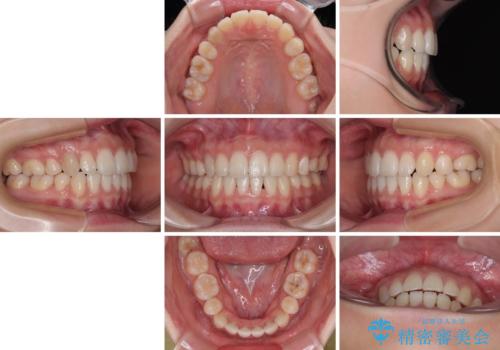

舌のトレーニングをしっかりと行ってくださり、予定通りの期間で理想的な仕上がりを達成することができました。

- 口元の突出感と上下前歯のズレを気にして来院された患者様です。

突出感改善のため、上下左右の第一小臼歯4本を抜歯し、ワイヤー装置にて矯正治療を行うこととしました。